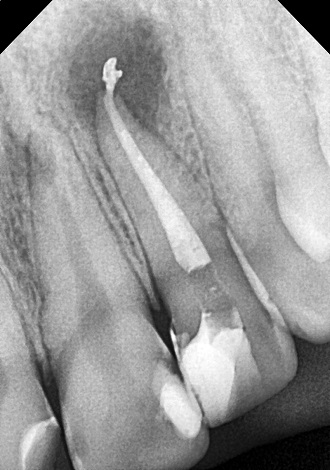

5. визначити глибину каналів зубного

кореня;

6. механічна розробка каналів;

7. хімічна обробка каналів;

8. герметична обтурація.

Пломбування кореневих каналів.

Якісно запломбовані кореневі канали є основою

довговічності. Тому очищення і пломбування кореневих каналів в «Домі Стоматології»

приділяється особлива увага! Після пломбування кореневих каналів проводиться

контроль якості пломбування за допомогою знімка.